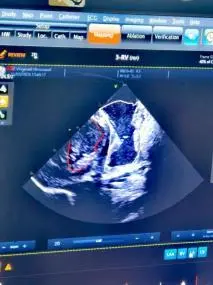

动物实验选用中型体重的猪,导管由穿刺颈静脉至上腔静脉进入心脏,无需动刀。建立入路后,先在心腔内超声指导下,完成心脏内部结构的电学重构,标记出希氏束、左右束支等心脏传导束的位置,走行路线,以希氏束导管为路标,指导无导线起搏器的植入。无导线起搏器到位后,由心腔内超声成像确认起搏器固定于心脏间隔,测试起搏参数。

图5.心腔内超声成像,确认无导线起搏器挂靠间隔的位置。